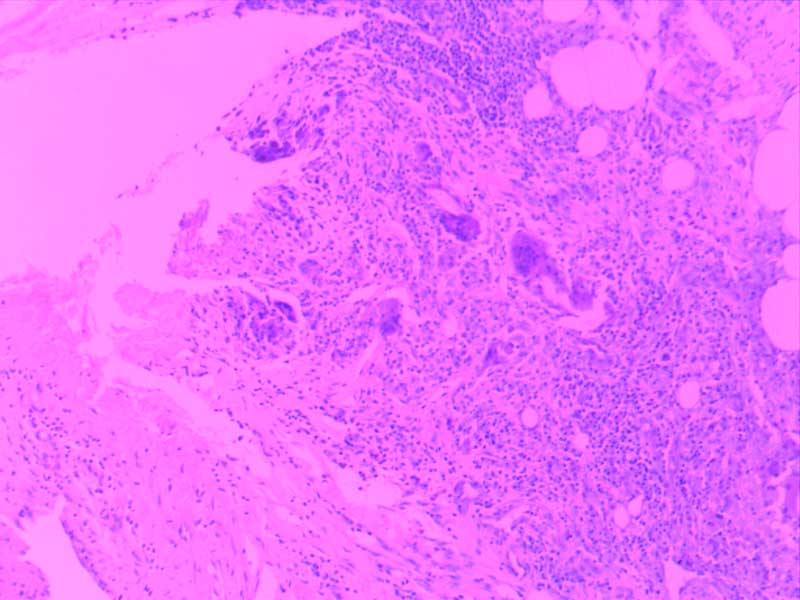

神经鞘瘤-10倍

肾透明细胞癌-10倍

肾细胞水肿-4倍

粟粒性肺结核

透明血栓-10倍

纤维肉瘤10-倍

纤维素性胸膜炎

小叶性肺炎-10倍-(2)

新月体肾炎-(2)

异物性炎-10倍

主动脉粥样硬化-4倍

主动脉粥样硬化-10倍